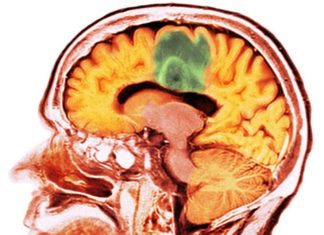

Rata de Supraviețuire în Cancerele Avansate ale Creierului se Dublează cu...